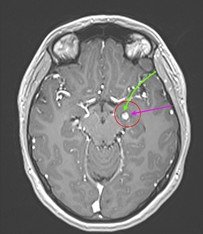

Pentru pacienți, aceste episoade sunt adesea greu de înțeles și pot fi însoțite de teamă și incertitudine. Investigațiile imagistice au adus însă explicația: RMN-ul cerebral a evidențiat o mică tumoră profundă, situată pe fața internă a lobului temporal stâng, la nivelul hipocampului și al nucleului amigdalian.

Deși tumora era relativ mică – aproximativ doi centimetri – localizarea ei era extrem de delicată. Hipocampul este una dintre structurile centrale ale creierului, implicată în memorie și procesarea emoțiilor, iar lobul temporal stâng joacă un rol important în limbaj.